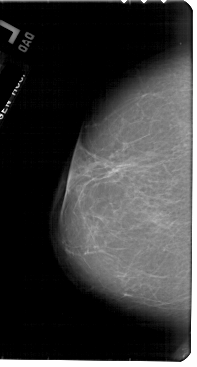

A_1904_1.RIGHT_MLO

RIGHT_MLO LINES 5491 PIXELS_PER_LINE 3436 BITS_PER_PIXEL 12 RESOLUTION 43.5 OVERLAY

FILE: A_1904_1.RIGHT_MLO.OVERLAY

TOTAL_ABNORMALITIES 1

ABNORMALITY 1

LESION_TYPE MASS SHAPE LOBULATED MARGINS OBSCURED

ASSESSMENT 4

SUBTLETY 2

PATHOLOGY MALIGNANT

TOTAL_OUTLINES 1

BOUNDARY